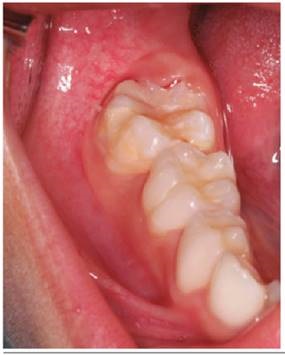

Luego de considerar las medidas de bioseguridad se procedió con el tratamiento de la pieza 46 (Figura 1), se realiza aislamiento relativo por la falta de erupción total de la pieza y la excesiva sensibilidad del paciente, aplicó brix 3000 (gel enzimático para la remoción a traumática de tejido infectado) (brix SRL Argentina), sobre las superficies infectadas de la pieza 46, luego de 2 minutos, con una cureta de dentina (Mayleffer N° 46) eliminamos estructura dental con HIM (Figura 2), se lavó con agua, y secó, se realizó desproteinización de la cavidad dentaria con una bolita de algodón embebida con hipoclorito de sodio al 5% por 30 segundos, y se enjuagó con una bolita de algodón embebida en agua, secado con bolitas de algodón (Figura 3), luego de cambiar el aislamiento relativo; se aplicó el adhesivo de 7ma generación Palfique Bond (Tokuyama), por la sensibilidad del paciente, se airea, fotocura por 20 segundos (Figura 4), y se aplica Giómero fluido F00 de reconstrucción (Beautifil Flow Plus de Shofu inc.), dando forma con el bruñidor para resina cabeza de huevo y se fotocuró por 20 segundos (Figura 5). Se utilizó el Giómero fluido F03 de sellado de fosas y fisuras (Beautifil Flow Plus de Shofu inc.) fotocurando por 20 segundos (Figura 6). Finalmente se comprueba el ajuste oclusal con una fresa cilíndrica plana (108-009) eliminando excesos y porosidades (Figura 7a).

Se realizó el control de la pieza dental a los 7 meses observándose en perfectas condiciones anatómicas y funcionales. (Figura 7b)